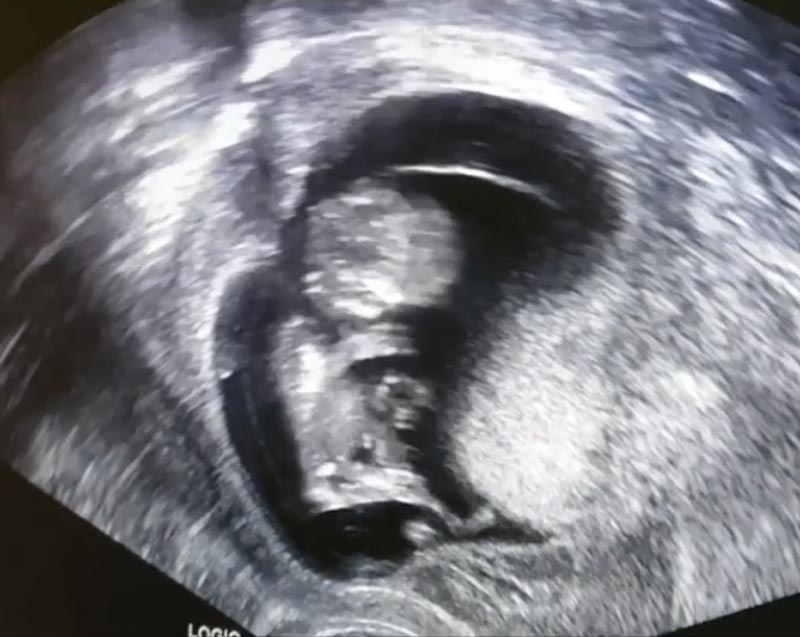

อย่างไรก็ตาม เมื่อเข้าไปดูในอินสตาแกรมของ ดีเจป๊อป ก็พบว่า เจ้าตัวเพิ่งออกมาโพสต์ถึงลูกคนที่สองพร้อมกับคลิปอัลตราซาวด์ลูกน้อยในท้อง เมื่อวันที่ 23 ตุลาคม 2562 ว่า ขณะขับรถไปจัดรายการทางภรรยาก็ได้โทร. มาบอกว่ามีเลือดไหลออกมาไม่หยุด ทำให้เขาจำเป็นต้องลาจัดวิทยุกะทันหัน และพาตัวภรรยาส่งโรงพยาบาลทันที ซึ่งตรวจพบว่า มีเลือดออกจากผนังด้านนอกของมดลูกประมาณ 10 เปอร์เซ็นต์ของพื้นที่มดลูกทั้งหมด และทำให้ภรรยาต้องนอนติดเตียง ต้องงดทุกกิจกรรม และพบแพทย์เพื่อรับยากันแท้ง ติดตามอาการเป็นระยะ

หนุ่มป๊อป ยังได้เผยว่า เป็นอีกหนึ่งในพันครั้งของชีวิตคู่ที่รู้สึกขอบคุณแม่ ๆ ในความเสียสละอันยิ่งใหญ่ แม้จะต้องยกเลิกทุกทริปที่วางไว้ แต่กลับทำให้มีความสุขกว่าการได้ไปเที่ยว นั่นคือการได้อยู่พร้อมหน้าบนเตียงน้อย ๆ ของพวกเรา ขอบคุณน้องของพี่ญามาที่อุตส่าห์ตื่นขึ้นมากระดุ๊กกระดิ๊ก ตอนอัลตราซาวด์ทำให้พ่อแม่สบายใจ ที่รู้ว่าลูกพ่อลูกแม่บ้านนี้เราจะต่อสู้ไปด้วยกัน พ่อ แม่ พี่ญามา รักหนูน้าคนเก่ง หนูคือของขวัญที่แสนวิเศษของครอบครัวเรา

ภาพจาก Instagram djpopkittiphong